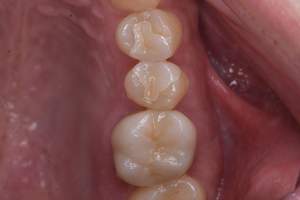

治療後:上の歯

担当医師所見:

左上第1大臼歯は抜歯し、仮歯に置き換えた後治癒を待ちジルコニアBrで補綴。また右上第1大臼歯は根管治療終了後にジルコニアクラウンで補綴。前歯部は審美性を考慮しジルコニアボンドにて補綴した。 色調、形態共に調和がとれている。

治療後:下の歯

下顎右側第1大臼歯は抜歯後、仮歯に置き換え治癒を待った後ジルコニアステイニングBrにて補綴。 全顎的に色調・形態共に調和がとれている。